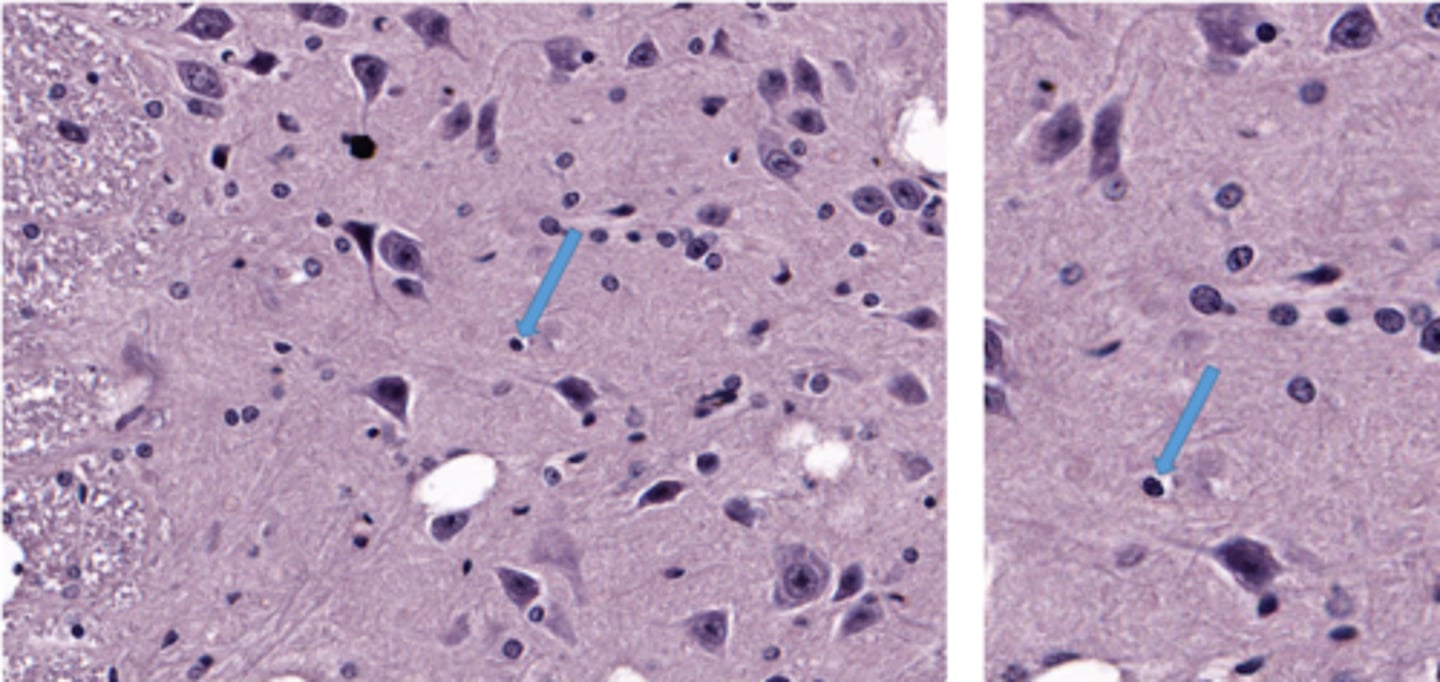

Identify this cell

purkinje cells in the brain

Identify the glial cell

oligodendrocyte

astrocyte

microglial cell

satellite cell

pyramidal cell